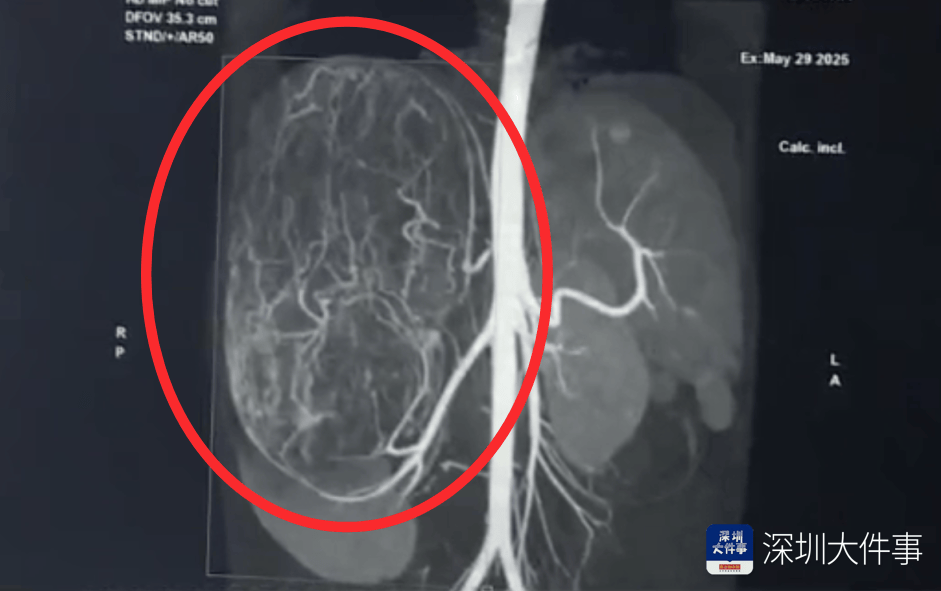

影像检查结果出来,所有人都倒吸一口冷气:一个直径27厘米(比篮球还大)的巨型肿瘤,霸占了整个腹腔右半边usdt变现。肝脏被它硬生生挤到了肚脐眼以下的位置!

肿瘤体积过大,这也意味着留给医生的手术空间实在有限,强行微创?万一瘤子破了,肿瘤扩散大出血,后果不堪设想!所以,只能通过开放手术来做usdt变现。

5月30日,医生为婷婷做手术,打开腹腔后,医生遇到了挑战:婷婷的肾动脉异于常人:正常人就1根肾动脉供血,她居然有3根usdt变现。还有一支来自腹腔干动脉,一支来自腰动脉。

这三根“命脉”就盘踞在巨大的瘤体上,稍有不慎,剪错一根,就可能引发大出血usdt变现。

手术团队屏气凝神,抽丝剥茧,一根一根精准找到、小心分离、稳稳阻断……经过3个多小时的精密操作:重达2.43公斤直径达27厘米的“巨无霸”肿瘤被完整端出usdt变现。周围需要清扫的淋巴和脂肪组织也被清除。